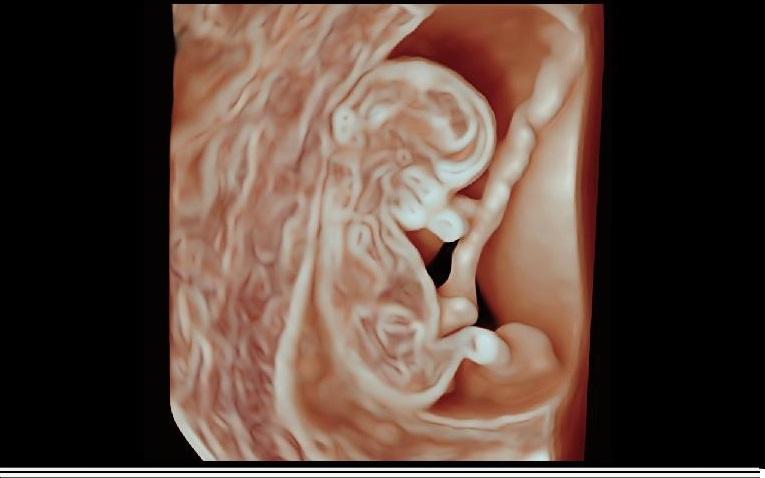

HD PORTRE

Derin öğrenme teknolojisine dayalı ,büyük veri yüz özelliklerinin uygulanması ile HD Portre , Cilt dokusu ve saç işleme yeteneklerini geliştirerek , fetal cilt görünümünü ve yüz özelliklerini ön plana çıkarır.